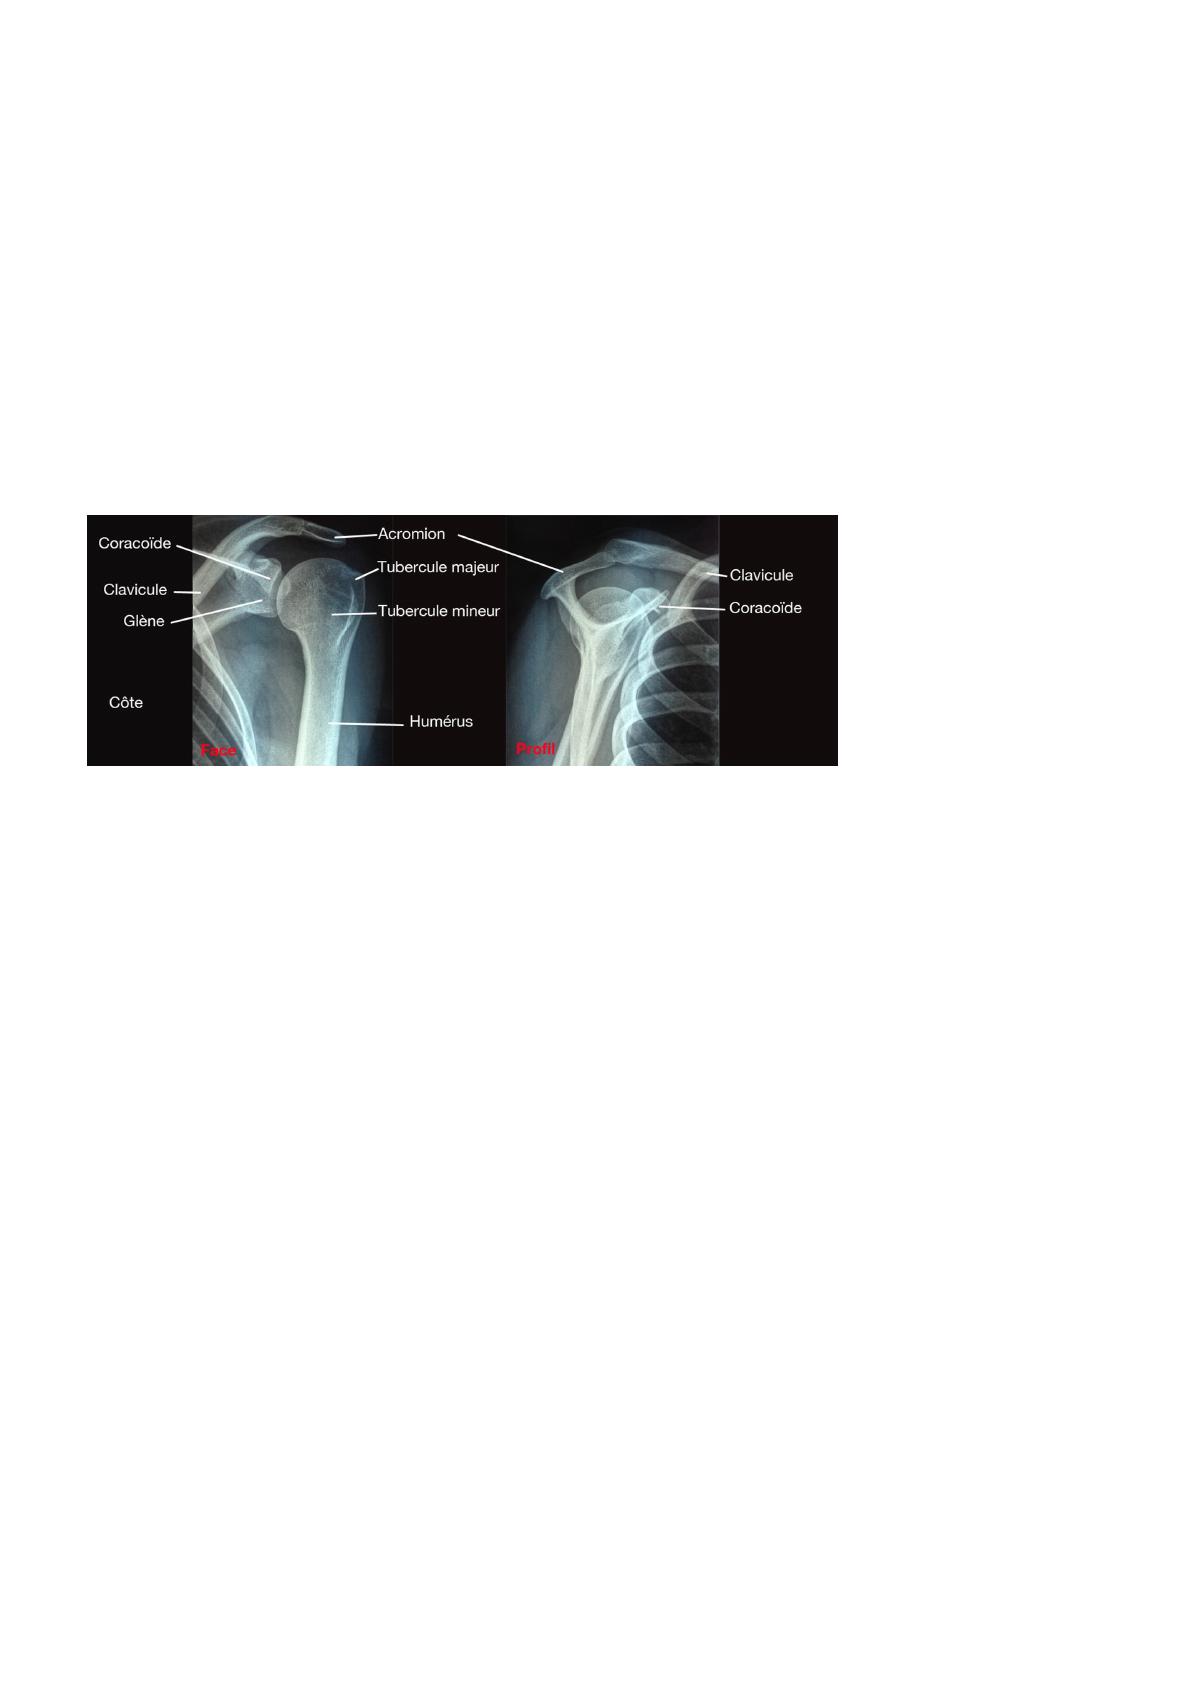

• Palpation: Palper systématiquement les repères osseux (clavicule, acromion, coracoïde, tête humérale) et les tissus mous (tendons de la coiffe,

long biceps, bourse sous-acromiale) pour localiser les points douloureux.